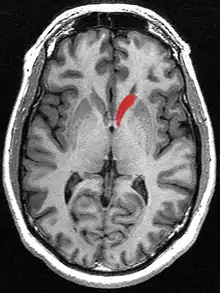

Transverse cut of brain (horizontal section), basal ganglia is blue | |

The caudate nuclei are near the center of the brain, sitting astride the thalamus. There is a caudate nucleus in each hemisphere of the brain. Each nucleus is C-shaped, with a wider "head" (caput in Latin) at the front, tapering to a "body" (corpus) and a "tail" (cauda). Sometimes a part of the caudate nucleus is called the "knee" (genu).[7] The caudate head receives its blood supply from the lenticulostriate artery; the tail of the caudate receives its blood supply from the anterior choroidal artery.[8]

The head and body of the caudate nucleus form part of the floor of the anterior horn of the lateral ventricle. The body travels briefly towards the back of the head; the tail then curves back toward the anterior, forming the roof of the inferior horn of the lateral ventricle. This means that a coronal section (on a plane parallel to the face) that cuts through the tail will also cross the body and head of the caudate nucleus.